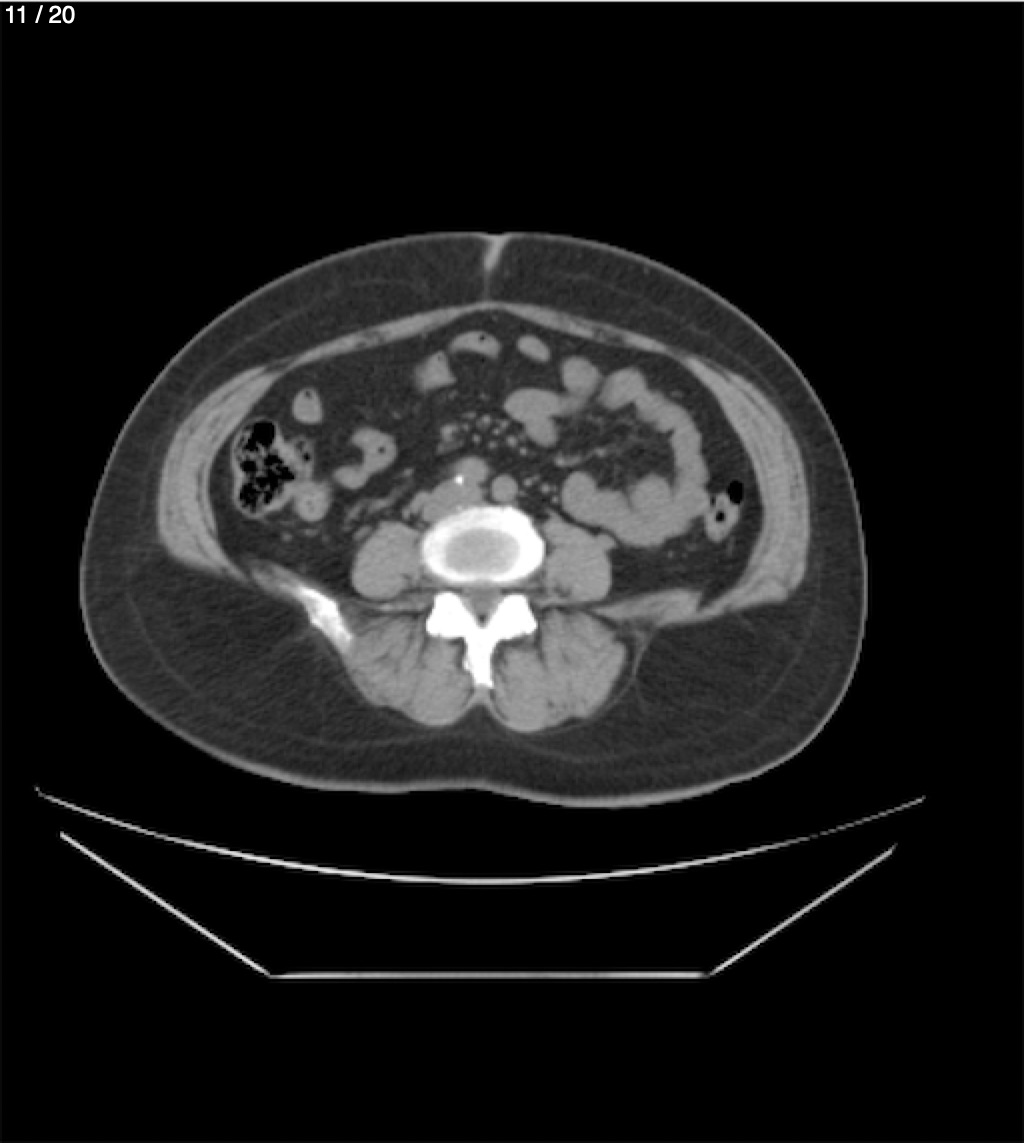

Maria Enrique Giron Dominguez63A - T.C Abdomen Simple